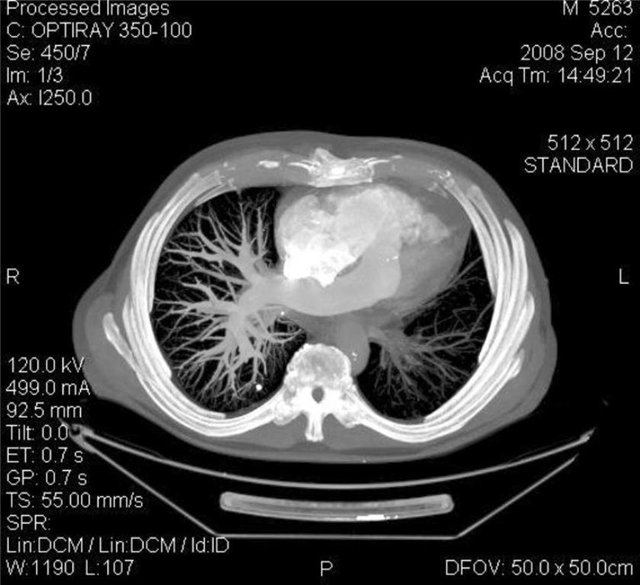

ТЭЛА как проявление АФС при волчанке. Высокое стояние купола диафрагмы справа, там же расширение корня и там же инфаркт пневмония.